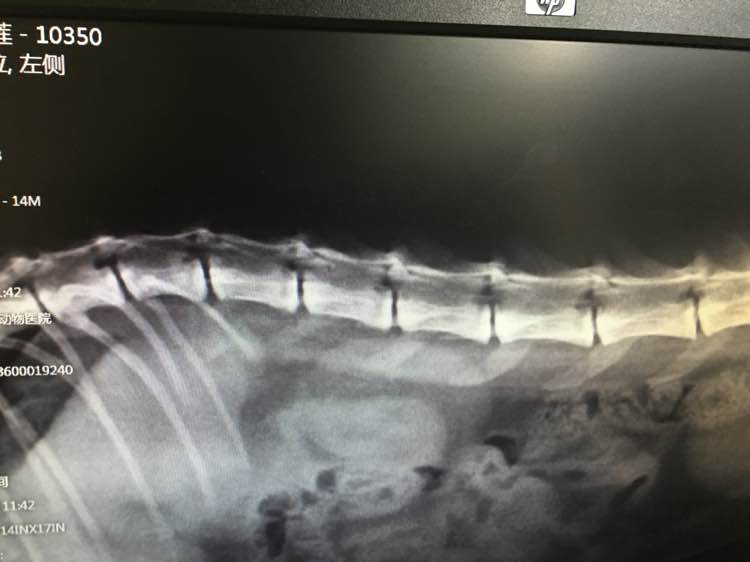

去医院检查了下,拍片 生化 血常规,说有可能是颈椎增生压迫神经或者是血栓,建议我再去拍一个ct或者去造影,但北京应该就一家医院能做,唉,我也没工夫带她去,只好现在家门口的医院住院治疗三天,输液什么的,看针剂基本是vc vb还有激素之类的,比如甲强龙,说明天如果反应良好会来一针神奇康肽,反正我也不太懂,只能尽人事听天命了⋯⋯

输了一天液,一些消炎止痛营养神经的药,然后还打了一针甲强龙,终于晃晃悠悠站起来了,还能走几步⋯⋯